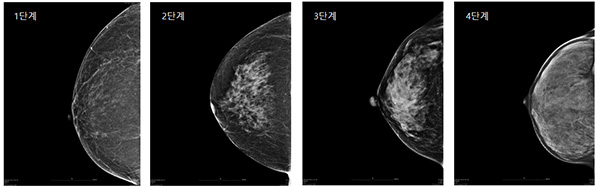

유방의 치밀도는 일반적으로 1단계에서 4단계로 나누어 보는데 , 3단계 이상의 치밀 유방은 유방 촬영 검사 시 유방의 50% 이상이 하얗게 나오는 경우입니다. 폐경 전 여성의 80%가 치밀 유방입니다.

폐경 전 여성의 경우 서양인의 약 70%가 저밀도 유방인 반면, 동양인의 약 90%가 고밀도 유방이라고 합니다.

서양인의 경우 지방 조직이 많은 유방이 많기 때문에 저밀도 유방이 많은 반면, 동양인의 경우 유선조직이 많은 유방이 많으므로 고밀도 유방이 많습니다. 그러므로 정기적인 검진을 통해 건강을 지키세요.